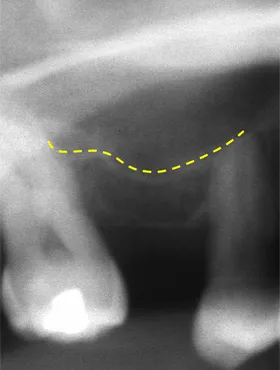

奥歯を1本長期間失ったケース

■治療前

向かって左の下の奥歯が、長期間失ったまま放置されていました。その為、向かって左奥の2本の歯が、前に倒れるように傾いてしまっていました。

まず、この傾きを治しました。治療期間は4ヶ月です。

■治療中

■治療中レントゲン写真

その後、歯を失った場所には、人工の歯根であるインプラントを埋めて、白い歯をかぶせました。

■治療後レントゲン写真

このようにして、従来なら前と後ろの歯を削って治していくブリッジにせずに、治すことができました。

| 主訴 | 右下の奥歯をずいぶん前に抜きそのままにしていたら、奥歯が倒れてきた |

| 治療方法 | 部分矯正治療+インプラント治療 |

| 治療期間 | 約10か月 |

| 通院回数等 | 12回位 |

| 費用 | 約80万円 |

| リスク・副作用 | インプラント術後の腫れ・痛み |